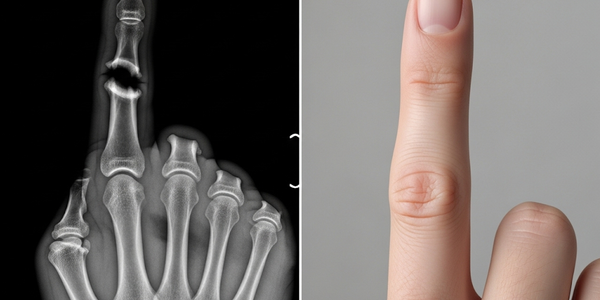

Может ли человек вырастить новый зуб с нуля? Ученые назвали главную проблему

Потеря зуба — событие почти ритуальное в жизни человека. Сначала мы с восторгом ждем Зубную фею, меняя молочные зубы на постоянные. Но когда во взрослом возрасте мы теряем зуб из-за...